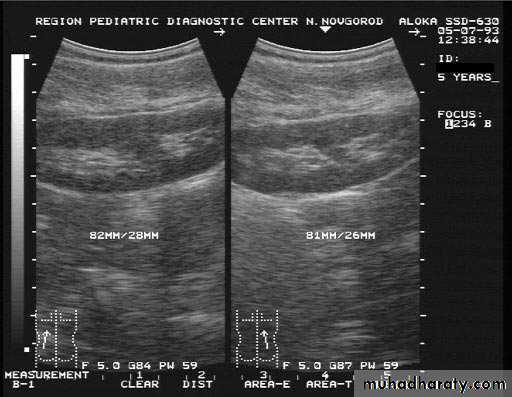

Ultrasound findings:

Division of renal sinus

duplication